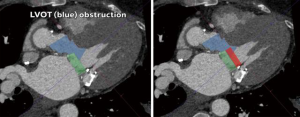

The proximity, and more importantly, the angle of the mitral valve annulus in relation to the LVOT further complicate TMVR. The device itself poses a risk of obstructing the LVOT. Additionally, the native anterior leaflet may cause obstruction being pushed anteriorly. This is akin to the obstruction of coronary ostia seen with TAVR, which is also gaining more recognition in the literature, and is particularly challenging if future access to the coronaries is needed. Several software packages and algorithms are currently available to obtain mitral annular sizing from cardiac computed tomography (CT) scans and to predict the extent to which a prosthesis will protrude into the LVOT (Figure 2). However, this is currently limited to making various assumptions and cannot reliably predict the extent of LVOT obstruction that will occur under dynamic conditions, potentially resulting in severe complications.